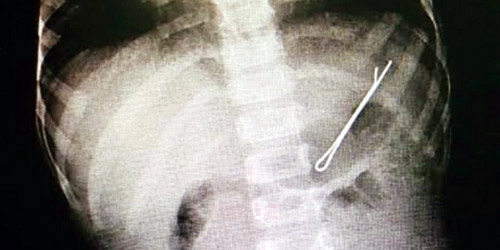

نجح الفريق الطبي بوحدة مناظير الجهاز الهضمي في مستشفى الولادة والأطفال ببريدة، باستخراج قطعة حديدية «مثبت للشعر»، من معدة طفل يبلغ من العمر سنتين.

وذكر رئيس الوحدة الدكتور عبدالعزيز الحربي، أنه تم إجراء العملية بنجاح والطفل يتمتع بصحة جيدة، منبهاً الأسر إلى ضرورة الاهتمام بمتابعة الاطفال وما يضعون في افواههم حتى لا يتعرضوا للاختناق.